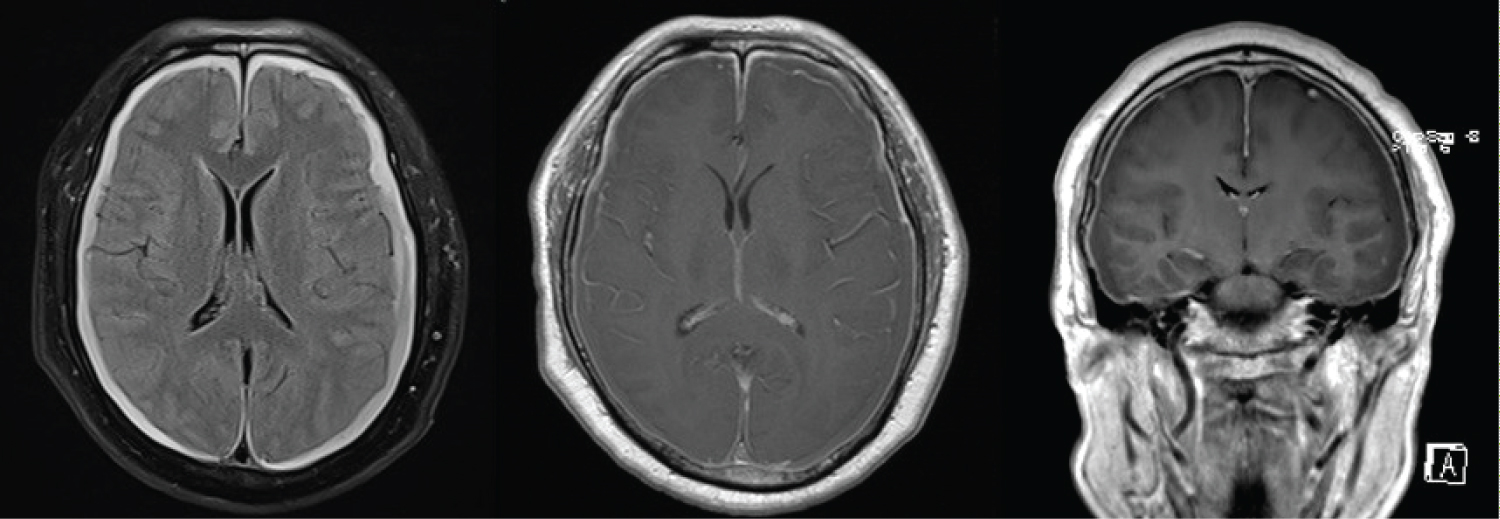

On this second presentation, clinical examination demonstrated diplopia that exacerbated with right gaze and left head tilt, consistent with worsening left trochlear nerve palsy. There were no other neurological deficits. CT-brain revealed bilateral subdural haematomas and mild obliteration of the suprasellar cistern with suggestion of sagging of the brain stem (Figure 1). Magnetic resonance imaging (MRI) of the brain showed bilateral holo hemispheric subdural haematomas (right 0.7 cm, left 1 cm) and sagging of the hypothalamus which raised the suspicion of intracranial hypotension. Diffuse pachymeningeal enhancement was seen (Figure 2). MRI whole spine was done. However, this failed to reveal any dural abnormality or extradural CSF fluid collection that would suggest a high flow CSF leak.

Figure 2: MRI-brain (A) Bilateral holohemispheric subdural haematomas; (B) Diffuse pachymeningeal enhancement; (C) Sagging of hypothalamus. View Figure 2